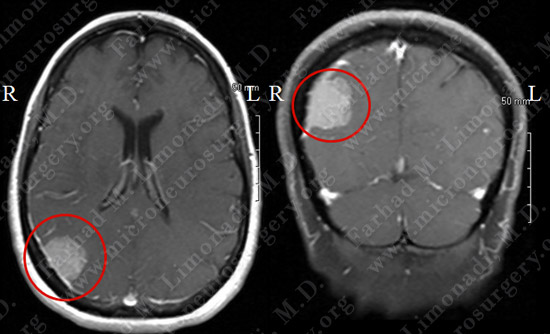

Imaging

MRI scan of the patient’s brain showed a right occipital brain tumor.

Before Operation                                                 After Operation